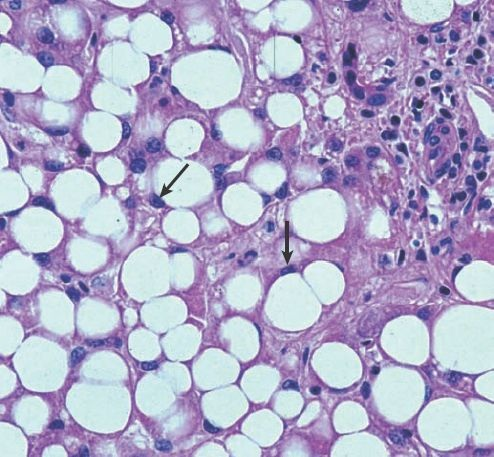

El hígado graso se caracteriza por la acumulación de grasa en los hepatocitos, condición que se denomina esteatosis (figura 46-12).

El hígado adquiere un color amarillo y aumenta su volumen debido a la acumulación excesiva de grasa. La patogénesis del hígado graso no se comprende del todo y pudiera variar según la cantidad de alcohol consumida, el contenido de grasas en la dieta, las reservas corporales de grasa, la condición hormonal y otros factores. Existe evidencia de que la ingestión de grandes cantidades de alcohol es capaz de inducir cambios propios del hígado graso, incluso con una dieta adecuada. Los cambios grasos que tienen lugar con la ingestión de alcohol no suelen generar síntomas y son reversibles una vez que el consumo de la sustancia se suspende.